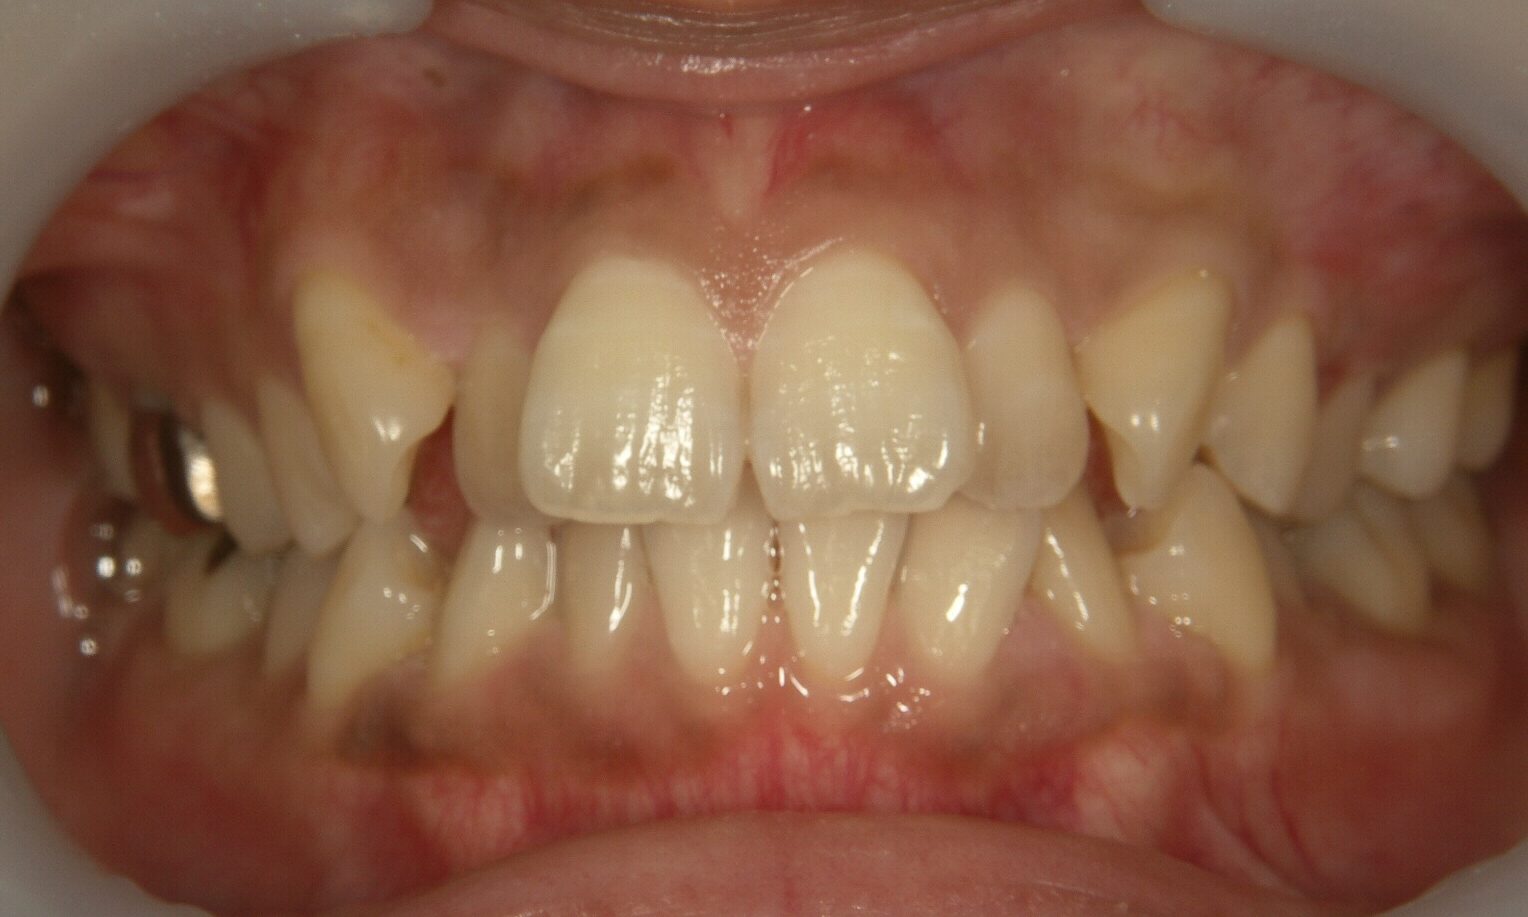

【症例1】重度の叢生(でこぼこ)を非抜歯で改善

「前歯が大きく重なり、他院で4本抜歯が必要と言われた」という30代女性のケースです。

- 治療方法: インビザライン・コンプリヘンシブ上下

- 治療期間: 1年6ヶ月

- 治療費用: 99万円(税込)

- 治療のリスク・デメリット 装着時間を守らないと期間が延長することがある

- ポイント: 抜歯をせずにIPRと遠心移動を組み合わせ、理想的なアーチを実現しました。